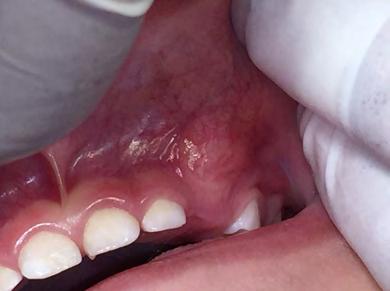

Figura 1. Fotografía de la zona de la lesión en la exploración clínica inicial. Se observa ausencia del canino superior izquierdo, ensanchamiento de la cortical vestibular y aumento de volumen.

Paciente masculino de 2 años 11 meses de edad., que se presentó a la consulta privada, la tía lo lleva a la consulta por falta de erupción del

canino superior izquierdo, a la exploración clínica se observó un aumento de volumen de campos profundos, blando y depresible, a nivel del canino superior izquierdo que se extendía hasta el fondo de saco y mucosa interna labial, así como, ausencia de la pieza dental sin antecedentes de extracción, No había dolor, sangrado ni secreción, asociados con el aumento de volumen.

El examen clínico reveló un aumento de volumen en la zona de órganos dentarios 63-65 que se extendía al seno maxilar, con desplazamiento de cortical vestibular, sin perforación ni cambio de color en la mucosa, de estructura uniforme bien delimitada. (Figura 1). En el examen radiográfico se observó la expansión de la cortical, con la presencia de múltiples dentículos. Desplazamiento del órgano